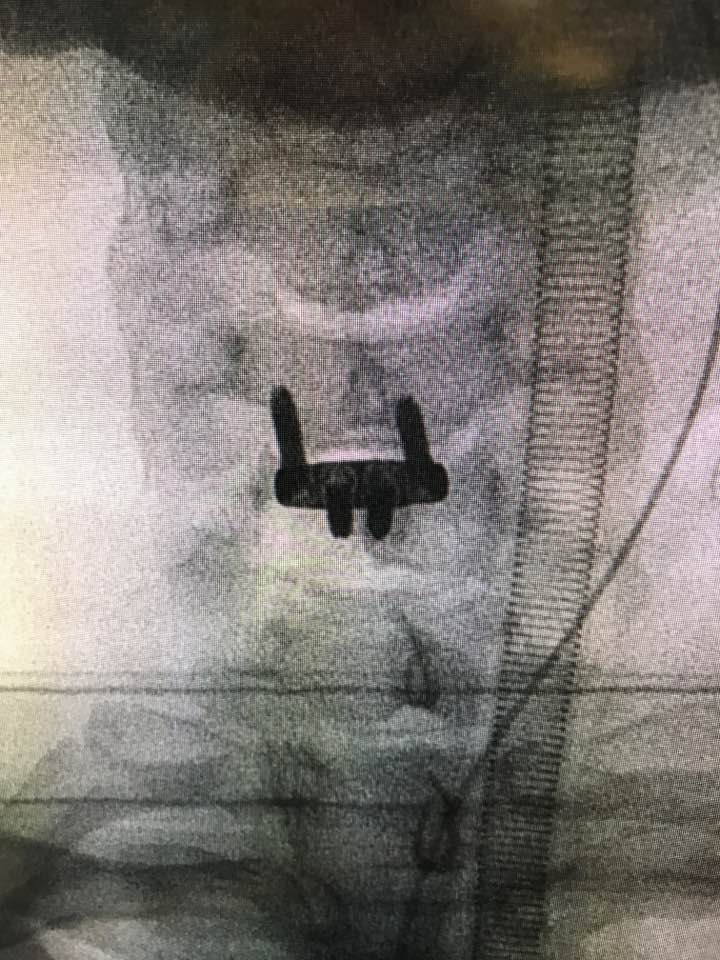

前路颈椎间盘切除及椎间融合和脊髓神经减压手术(ACDF)

手臂因椎间盘突出,压迫脊髓神经而无力

刚刚完成,又是在星期日的手术